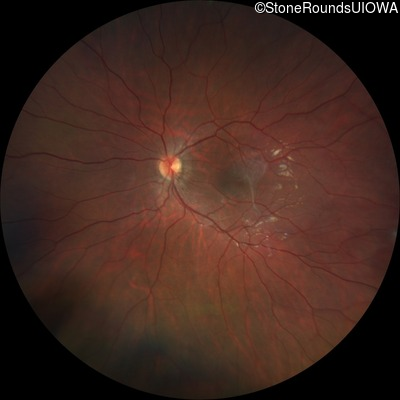

This 9 year old male was noted to have some crossing of his eyes at 2 months of age and the eye exam which followed identified a retinal lesion in the right eye. When he was six years old an epiretinal membrane was noted in his left eye. Two years later it was decided that it was a thin hamartoma in that eye as well. He underwent neuroimaging at age 7 which identified bilateral acoustic neuromas.

| Age at visit: 7 years |

| Age at visit: 8 years |

| Age at visit: 10 years |

| Age at visit: 11 years |

| Age at visit: 14 years |